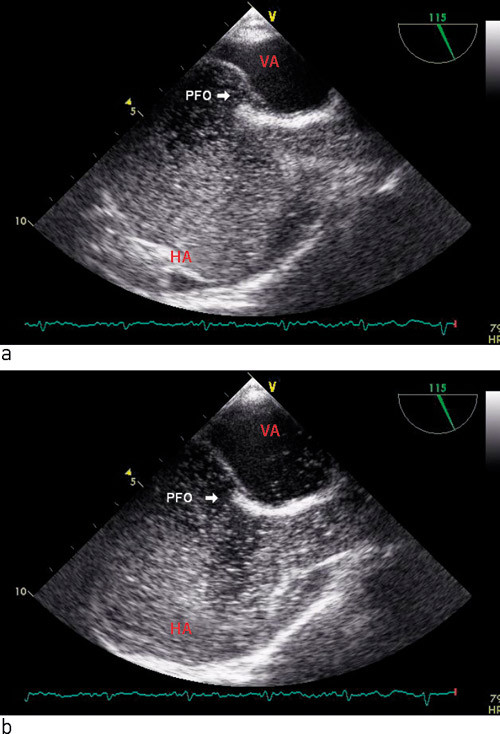

Transøsofageal ekkokardiografi med injeksjon av saltvann med mikroluftbobler i perifer vene regnes som gullstandard for deteksjon av åpent foramen ovale (fig 2a). Påvisning av bobler i venstre forkammer innen 3 – 4 hjerteslag etter injeksjonen regnes som kvalifiserende for at shuntingen skjer direkte interatrialt (fig 2b). Fenomenet er også illustrert i en video i nettutgaven. Deteksjon av bobler i venstre atrium senere enn dette antas å skyldes resirkulasjon eller intrapulmonal shunting. I sammenliknende studier mellom autopsi, transøsofageal ekkokardiografi og transtorakal ekkokardiografi med kontrast har transøsofageal ekkokardiografi vist en sensitivitet på 89 – 100 % og en spesifisitet på 100 % (9, 10). I tillegg til å påvise atriale shunter kan metoden gi anatomisk informasjon om størrelse og form på åpent foramen ovale og påvise atrieseptumaneurisme, som er en viktig risikofaktor for paradoks embolisering (11).